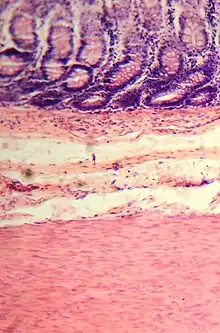

Le gros intestin est le dernier segment du tube digestif des vertébrés. Il fait suite à l’intestin grêle et s’étend de la valvule iléo-cæcale à l’anus ou au cloaque. En anatomie, il est divisé en deux parties : le côlon et le rectum (plus parfois le canal anal)[1],[2].